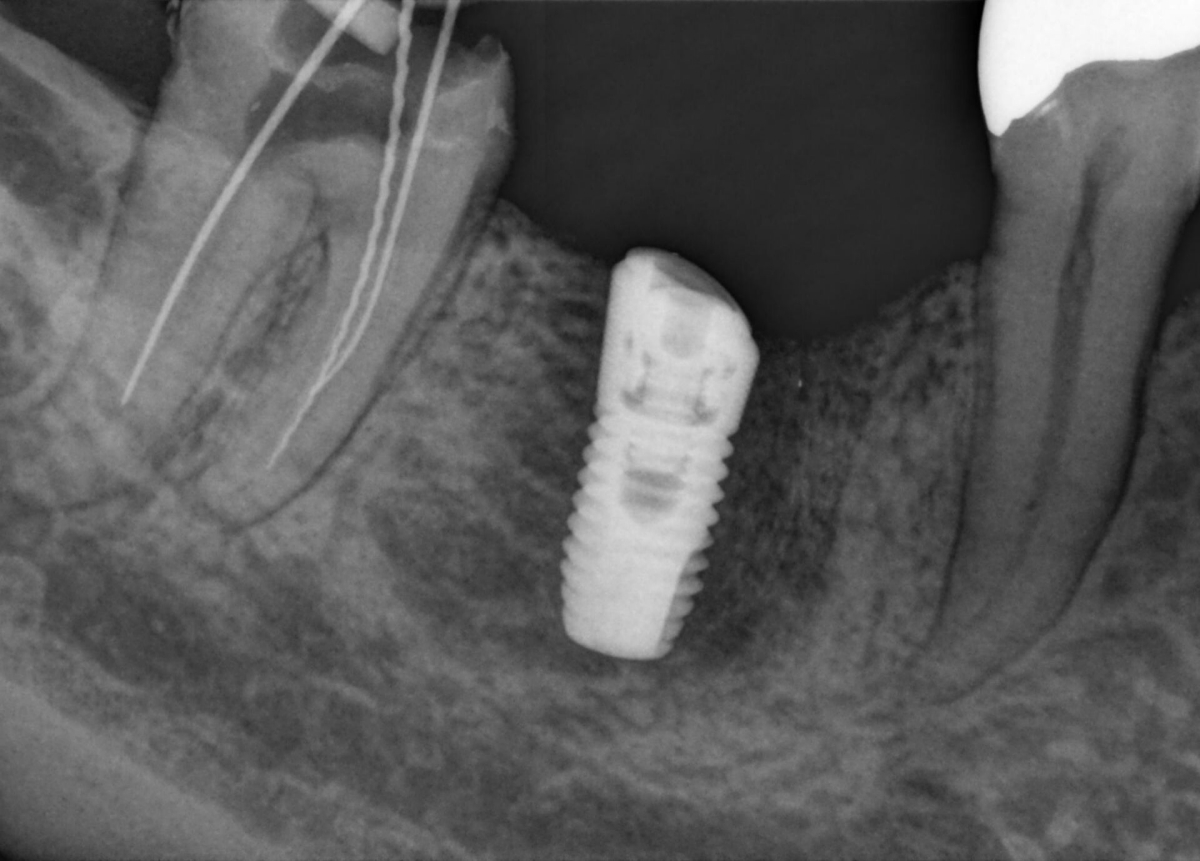

MARS – Metal Artifact Reduction Software

Metal artifacts are a challenge in 3D X-ray imaging. Radiopaque objects create shadowing and streaking effects during the three-dimensional reconstruction and as such interfere with the findings. MARS automatically reduces metal artifacts and facilitates the diagnosis.